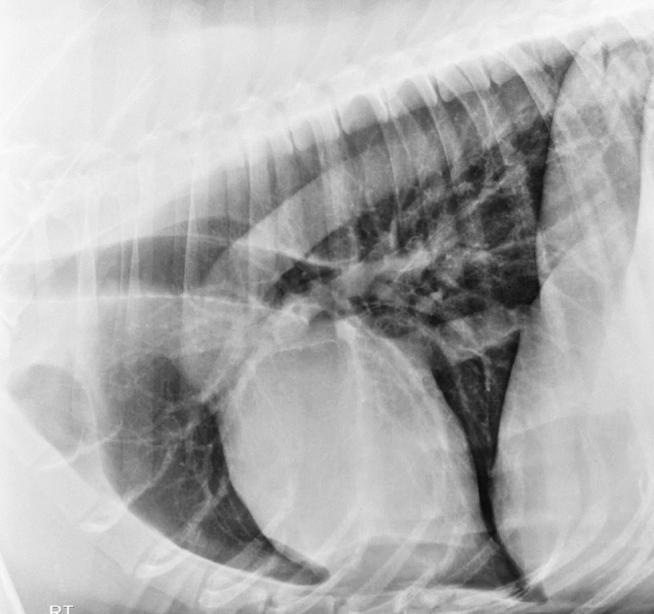

52

Lung Pattern?

Pleural effusion

53

Moderate right-sided pleural effusion